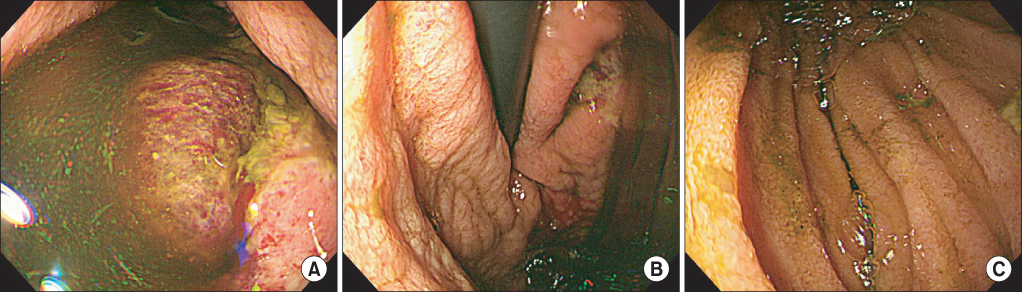

On the patient's third day in hospital, upper gastrointestinal tract endoscopy revealed many geographic ulcers with mucosal hemorrhages in the body of the stomach. There was marked dilatation of the second segment of the duodenum with many geographic ulcers and a collapsed third segment associated with the SMA syndrome (Fig. 2). An intravenous proton pump inhibitor was administered to treat the peptic ulcer bleeding.

On early endoscopy, bubbles with a 'cobblestone' appearance can be seen in the gastric mucosa of patients affected with gastric emphysema or emphysematous gastritis [18]. Endoscopic findings in such patients include submucosal gas bubbles, necroinflammatory changes, and erosions [19]. In some cases, the mucosa appears normal [19]. In our case, in order to avoid barotrauma to the stomach, upper endoscopy was not done immediately. On the third day of hospital, when the patient's physical condition became stable, upper endoscopy was performed very carefully. This demonstrated many gastric ulcers with mucosal hemorrhage in the body of the stomach. There were no mucosal bubbles or necrotic changes.

Upper endoscopy. It shows many geographic gastric ulcers with mucosal hemorrhage in the body of stomach (A, B), and collapsed third segment associated with the superior mesenteric artery syndrome (C).

Fig. 2 Upper endoscopy. It shows many geographic gastric ulcers with mucosal hemorrhage in the body of stomach (A, B), and collapsed third segment associated with the superior mesenteric artery syndrome (C).